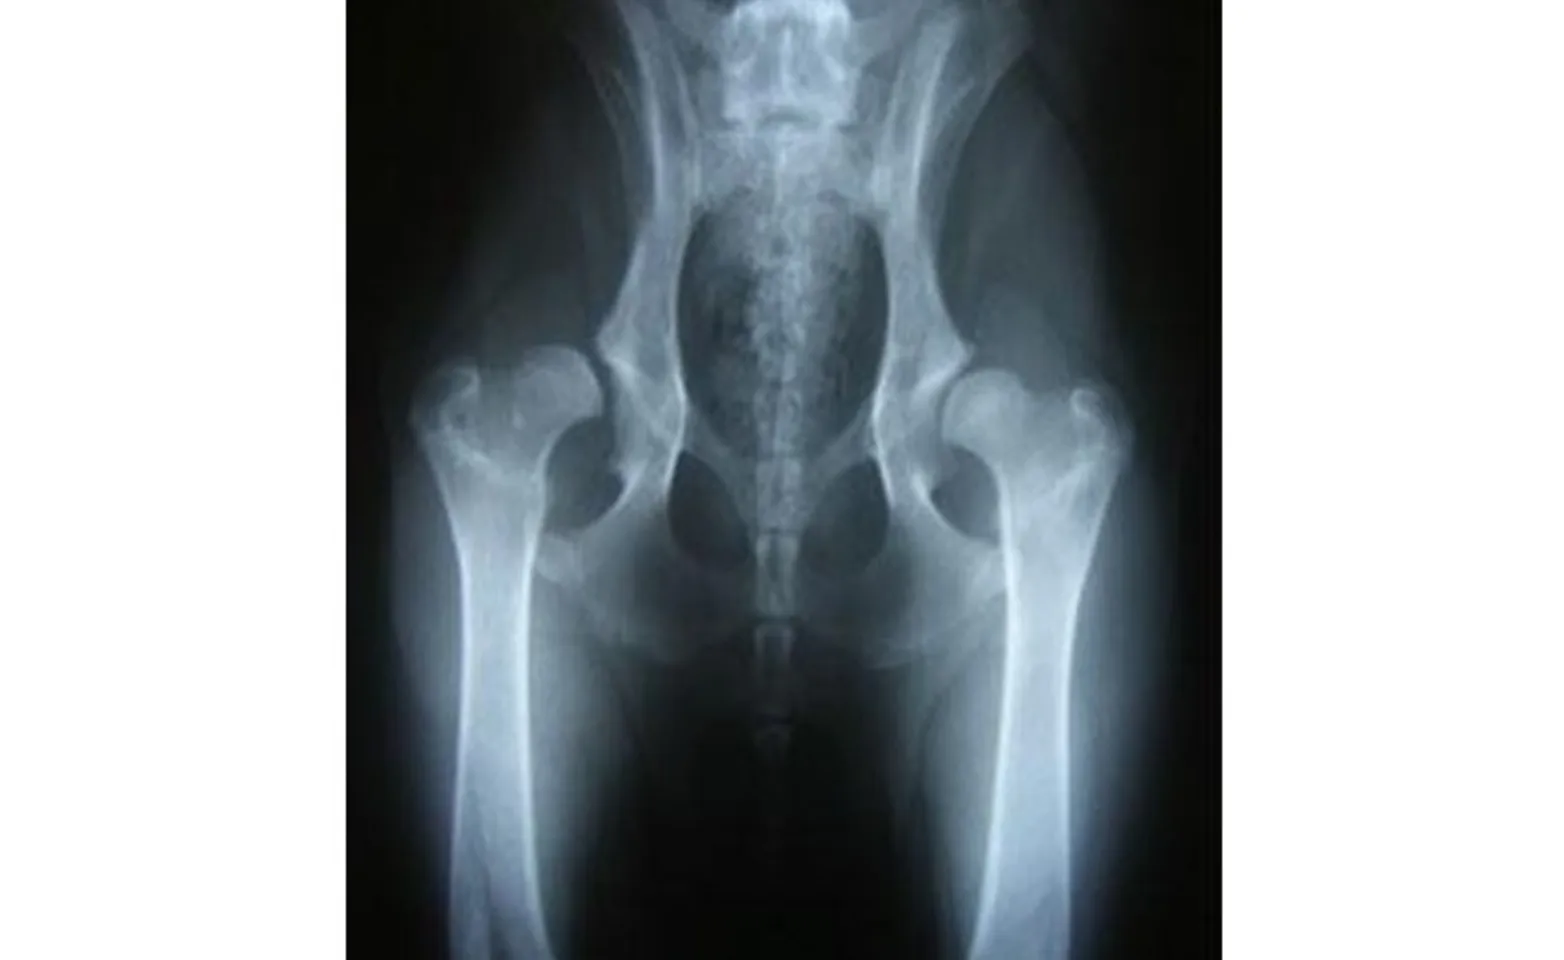

As the condition progresses, there may also be early signs of remodeling or flattening of the femoral head, and the acetabulum may become more shallow (Figure 3).

Figure 3: Radiograph showing a young dog with severe hip subluxation secondary to joint laxity.